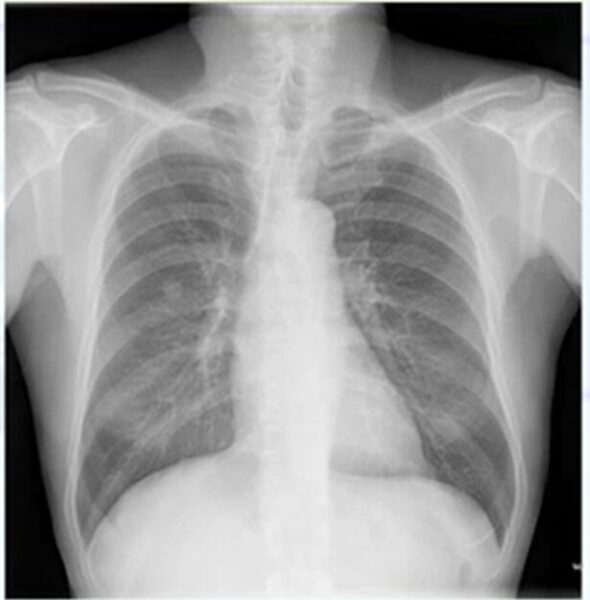

肺癌のレントゲン(X-p)写真

肺癌のレントゲン(X-p)写真の特徴を共有します。検診などでレントゲンを撮ることは多いと思います。医師が責任をもって読影しますが、どのような特徴をもとに読影をしているのか共有しておきます。

本症例では右中肺野に結節影を認め、肺癌が疑われ、精査に進めます。

読影のポイントとすると、もともとある構造物が重なって濃度症状をきたすもの(骨と骨・血管と骨の重なりなど)。は異常か正常かX-pでは言えませんので、過去の写真と比較して、1年前なかった(肺癌)、1か月前なかった(結核)、1週間前なかった(肺炎)を考えます。